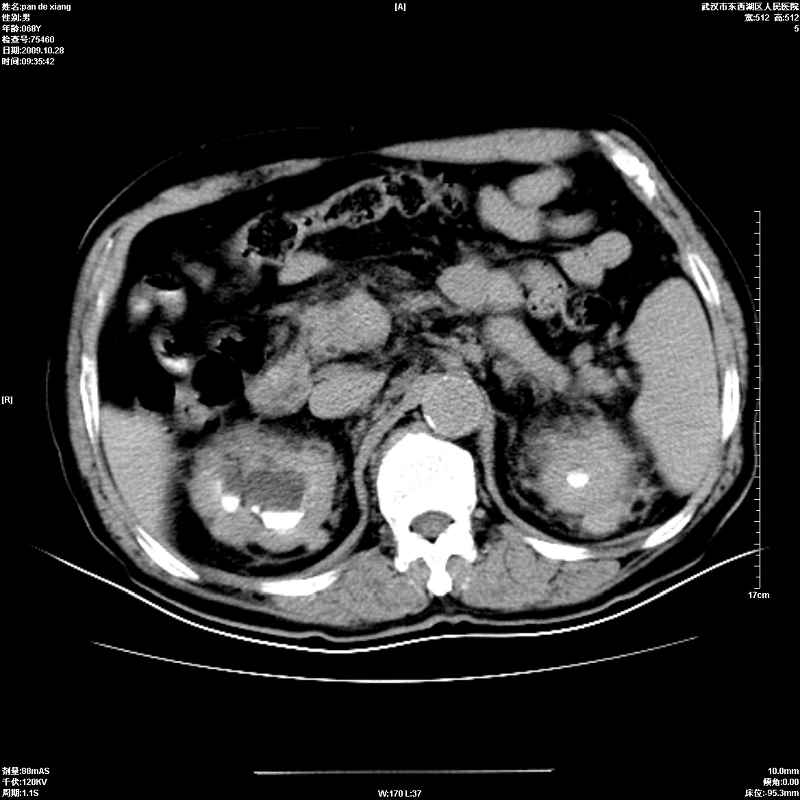

以下是引用杀毒软件在2009-10-28 20:41:00的发言:[br]结合临床考虑---白血病双肾改变或淋巴瘤。

以下是引用zxl51642在2009-10-29 9:59:00的发言:[br]结合临床“单克隆免疫球蛋白血症”,考虑双肾为继发损害并肾功能不全(尿中大量igg及少量iga、igm等大分子免疫球蛋白滤出所致继发损害),椎前软组织肿块为髓外造血。与浆细胞瘤有区别,平扫时有战友说的很清楚。